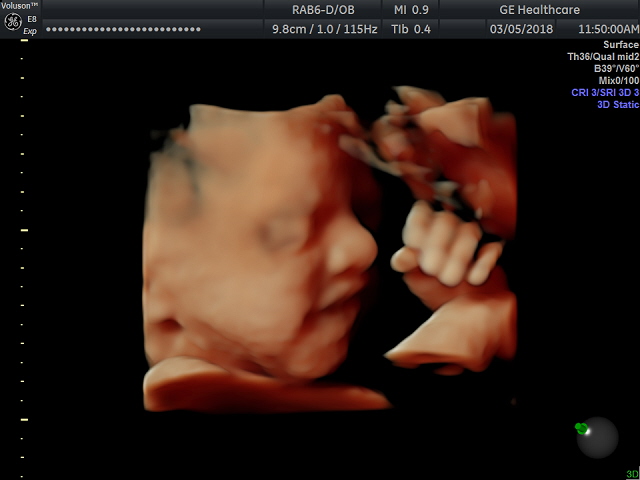

We started off this week with an exciting teaser of our little girl. By no means is this a finished product, but at 29 weeks, our little looks just like her Dad already. 🙂 It was easy to get in the babymoon spirit after seeing these incredible HD images.